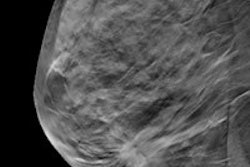

Digital breast tomosynthesis (DBT) continues to be a hot new modality. Two studies from this month's International Congress of Radiology (ICR) find DBT is superior to conventional digital mammography when detecting breast cancer in women with dense breasts. And the modality has an edge for the characterization of masses.

Just how much superior is DBT? And in what category of dense breasts does it work the best? Find out.

In another DBT study, a breast screening protocol that combines single-view DBT with single-view 2D digital mammography had higher sensitivity for detecting breast cancer than two-view 2D digital mammography, with just a slight increase in radiation dose, according to a new study in European Radiology. Read more.